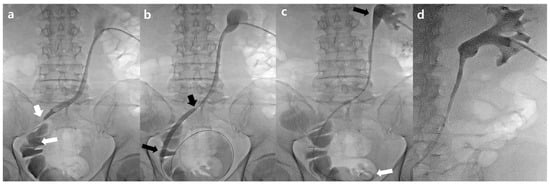

2.2. Procedure